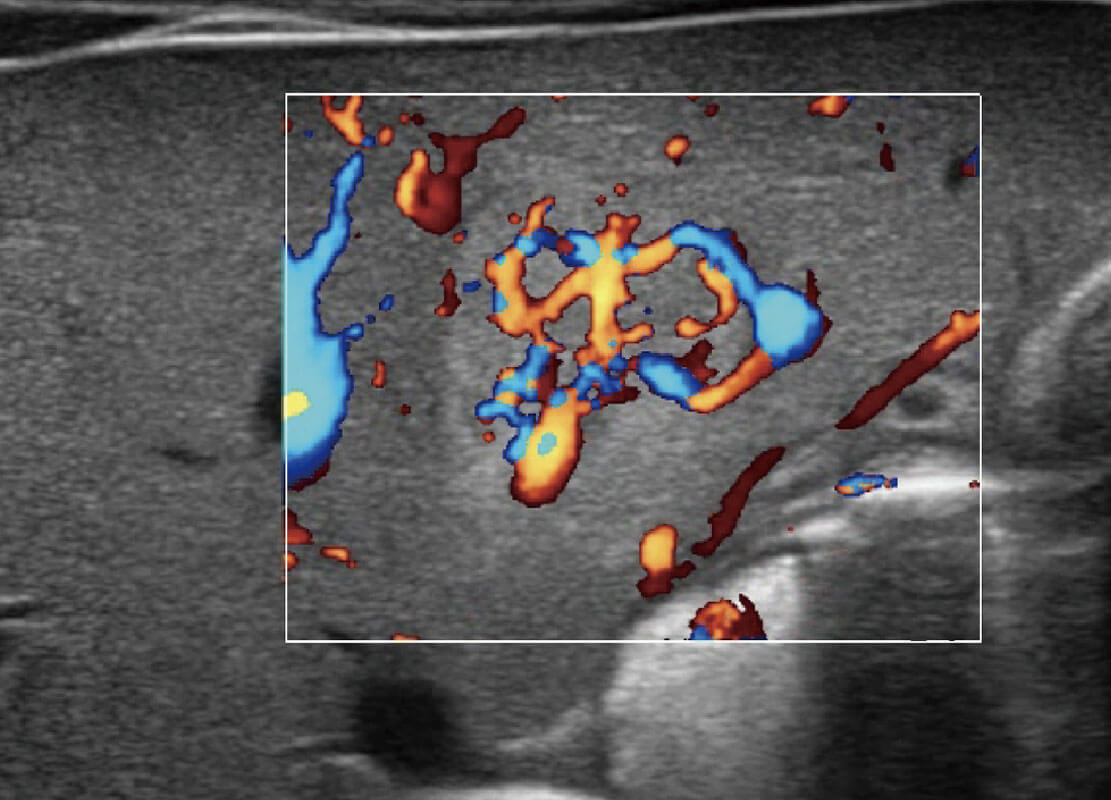

• 胎儿体循环

乳腺超声 / 新生儿

P60搭载宽频带线阵探头、宽景成像、弹性成像技术,为您提供乳腺应用方案。P60支持高频相控阵探头、线阵探头、腹部高频探头、腹部微凸探头等,丰富的探头群搭载敏感的彩色血流成像,适用于新生儿多种脏器检测要求,满足新生儿筛查需求。

• 乳腺癌显微血流